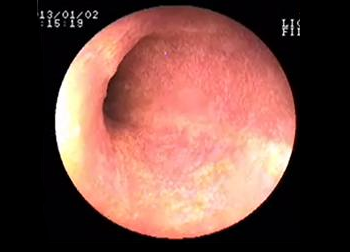

진단을 위해 기본적으로 각종 정밀 혈액검사와 요검사, 방사선검사, 초음파, 내시경 등을 실시하게 되며 치료는 진단된 질병을 바탕으로 약물 치료를 기본으로 하며 관리가 어려운 신장질환의 경우 혈액 투석을 실시하고 있습니다.

- 내시경(상부/하부)

- 조직검사 / 귀 내시경